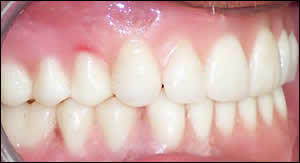

Fig 10: Right intraoral view in centric occlusion.